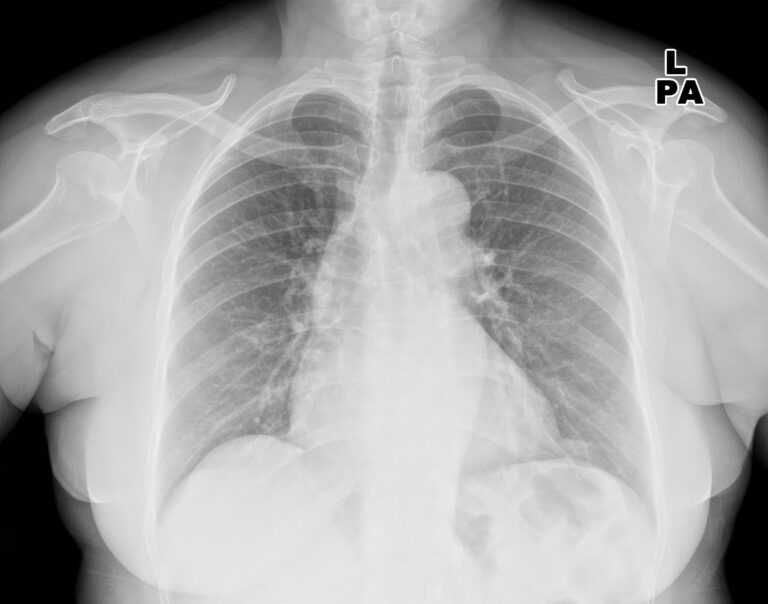

Examine: Commercially Obtainable Chest Radiograph AI Instruments for Detecting Airspace Illness, Pneumothorax, and Pleural Effusion. Picture Credit score: KELECHI5050 / Shutterstock